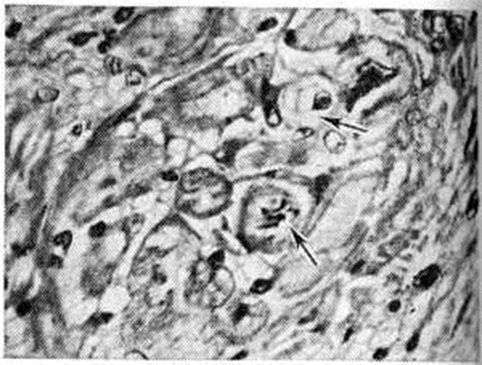

В заключительной стадии поражены обширные участки миокарда обоих желудочков, особенно — левого. В основном выявляются дистрофические и некротические изменения миокардиоцитов, начиная от вакуолизации перинуклеарной зоны цитоплазмы (смотри полный свод знаний Вакуолизация) и до цитолиза (рисунок 2) с полным растворением тел клеток (смотри полный свод знаний Цитолиз). От клеток остаются только следы в виде мелких зёрен липофусцина. В результате образуются ареактивные участки депаренхимизации миокарда (рисунок 3) с так называемой пустой сеткой, в дальнейшем замещаемые соединительной тканью. Ряд мышечных волокон подвергается мелкоглыбчатому и мелкозернистому распаду с образованием фуксинофильного детрита, резорбция которого также заканчивается миофиброзом. Процесс вакуолизации и лизиса распространяется и на клетки эндотелия кровеносных сосудов в очагах поражения. Процесс в целом напоминает дистрофический (деструктивный) миокардит. Нередко обнаруживаются также воспалительные лимфогистиоцитарные инфильтраты с примесью сегментоядерных лейкоцитов; в сочетании с дистрофическими изменениями создаётся картина смешанной формы идиопатического (аллергического) миокардита. Внутриорганные мелкие артерии и артериолы изменяются по типу аллергического васкулита (смотри полный свод знаний) — от фибриноидного некроза стенки (рисунок 4) до облитерирующего панваскулита. Все эти процессы обнаруживаются на фоне распространённых полей кардиосклероза различной зрелости (рисунок 5), подобно миокардитическому кардиосклерозу (смотри полный свод знаний Кардиосклероз), что свидетельствует о прогрессирующем и длительном течении поражения миокарда. В дистрофический и рубцовый процессы вовлечены и различные отделы проводящей системы с миоцитолизом (рисунок 6).

Рис. 6. | ||